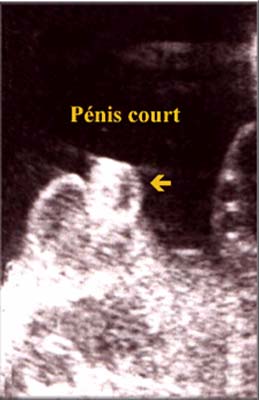

L’hypospade distal doit-être suspecté chaque fois que le pénis paraît court et/ou incurvé ( incurvation latérale ou ventrale) ou de forme anormale ( extrémité de forme bulbaire).

Il faut cependant noter qu’une incurvation du pénis peut-être isolée sans hypospadias.

Cette découverte doit faire rechercher d’autres anomalies associées et isolée elle est de bon pronostic.